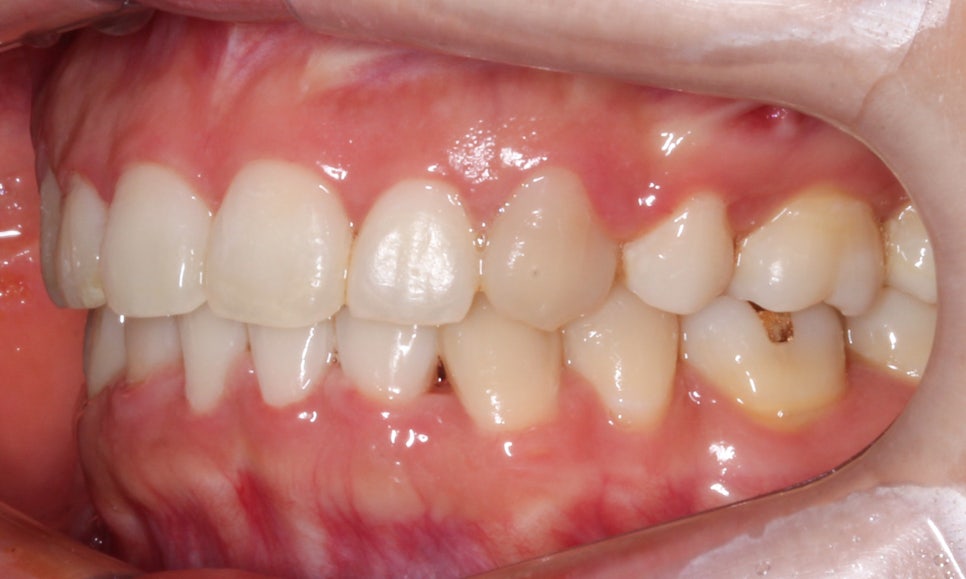

송곳니덧니 case의 좌우 교합평면 사진입니다.

측면에서 치아의 높이를 보면 보다

명확하게 high canine 증상을 확인할 수 있는데요,

송곳니는 우리의 치아 가운데 가장 길이가 긴

치근을 가지고 있기 때문에 성공적인 교정

결과를 기대하시는 경우 이 송곳니의 위치를

올바른 위치로 이동시키는 것이 중요합니다.

또한 사진에서 작은어금니와 잇몸 사이의

경계 부분에 나타나는 치아의 파임 증상은

치경부마모증이 일부 진행된 것으로 보이는데요,

위처럼 법랑질만 미세하게 손상된 초기일 경우

레진이나 Gi 치료만으로 수복이 가능하나

상아질까지 손상된 경우에는 크라운 등

넓은 범위의 보철치료가 필요할 수 있습니다.